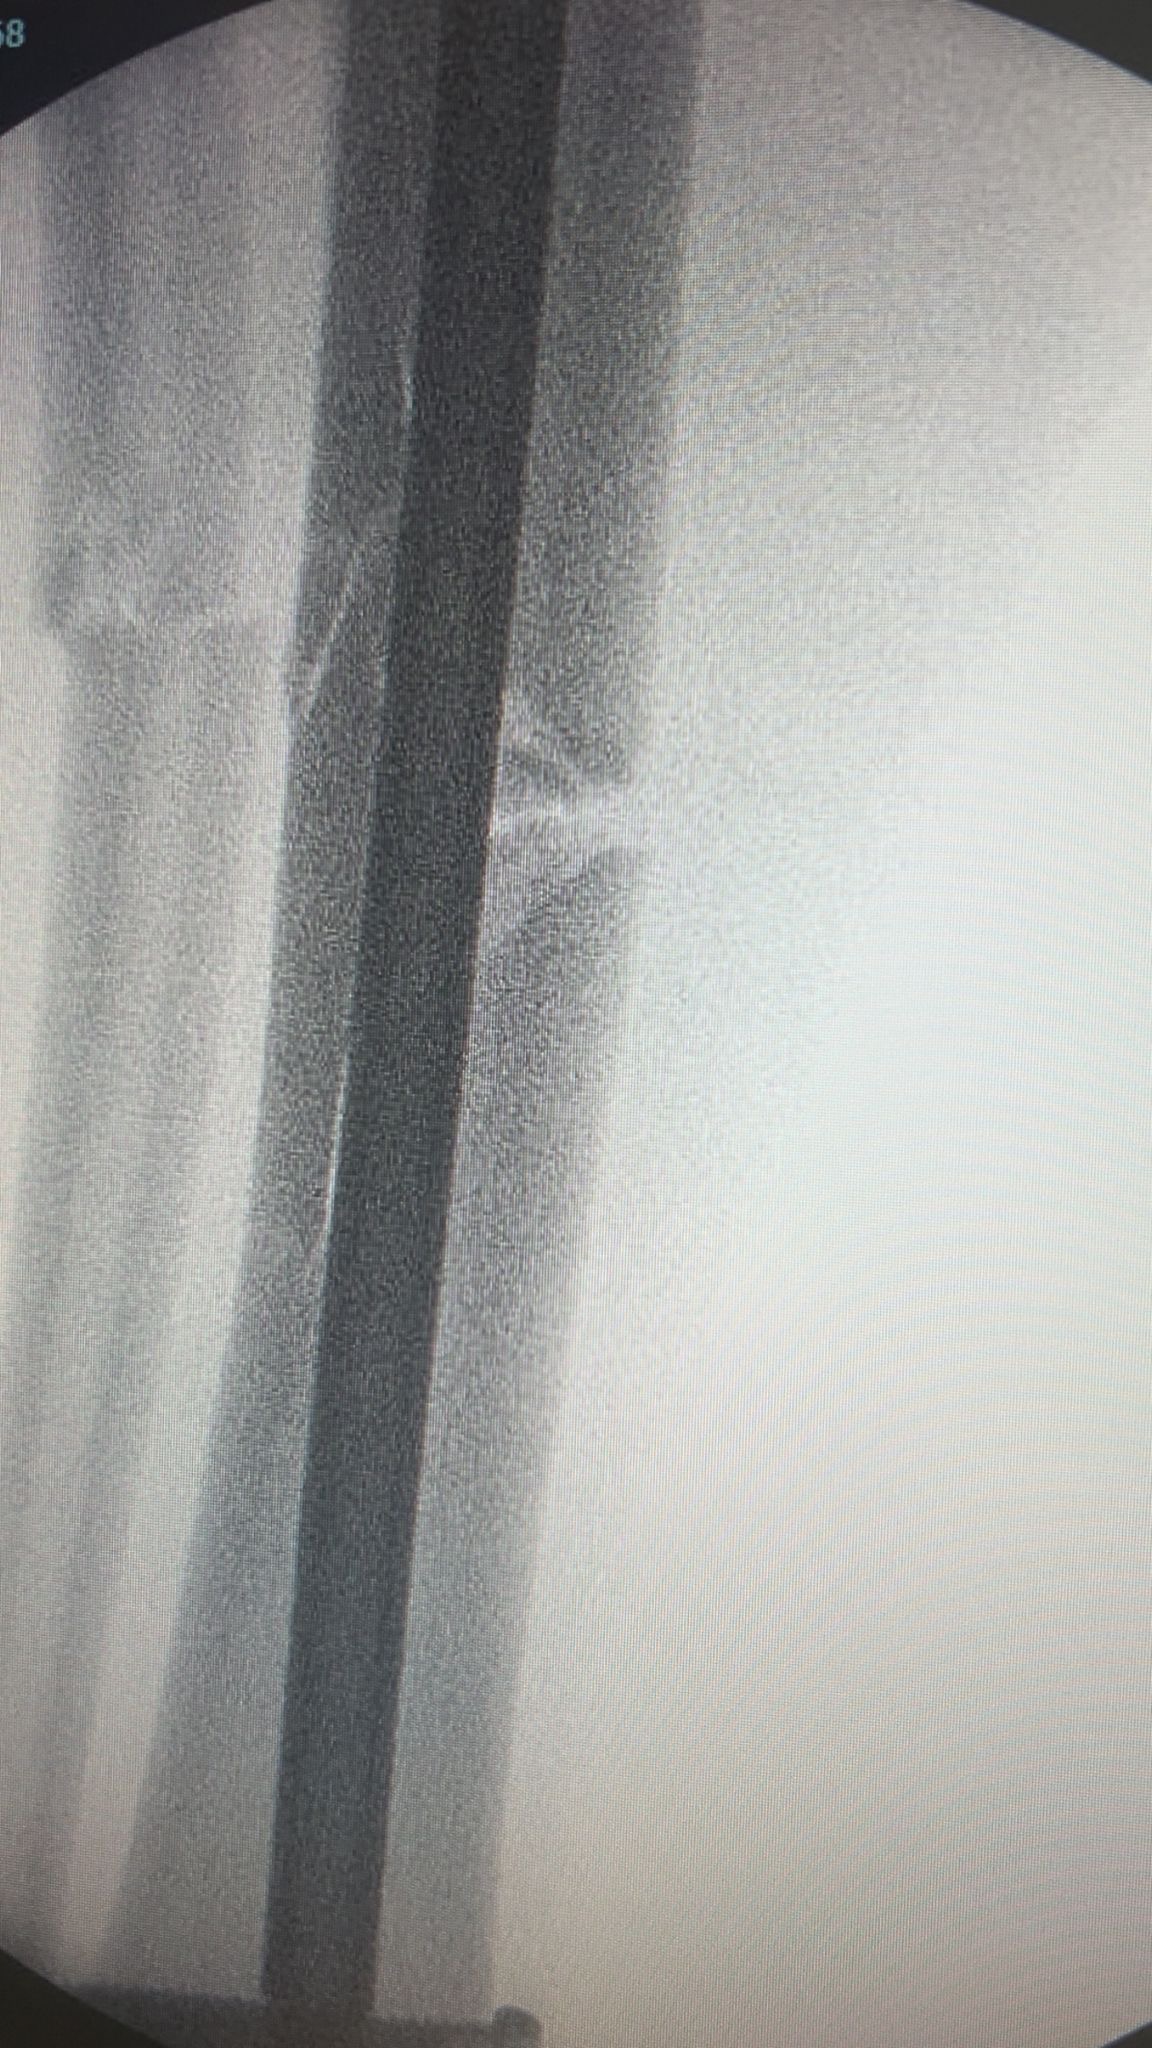

On Saturday 25th October, one of our men’s teams were playing a league match against Montpellier Reserves. During this match one of our players, Josh Swales, unfortunately suffered a triple leg fracture during a horrific tackle. The match was abandoned and Josh was rushed to hospital. In hospital Josh was put into a cast and transferred to Gloucester Royal Hospital. On Monday 27th October, Josh had surgery to insert a metal rod and 4 screws into his leg. On Thursday 30th October, Josh was discharged with crutches to continue recovery from home. He was told he would be unable to put full weight through the leg for at least 6 weeks, be off work for 8-12 weeks and out of any exercise for 4-6 months.